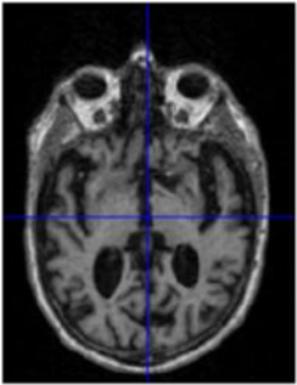

To display how the DWT performs on an MRI scan, the 2-D DWT performed on a 2-D slice of a 3-D MRI scan. Four subbands were generated by a low-pass or high-pass filter being performed on each of the two dimensions in 2-D image. Each subband is represented as a two-letter key, representing what subbands are in which dimension. An “a” represents an approximation subband produced by a low-pass filter and a “d” represents a detail subband produced by a high-pass filter. Figure 2 shows the four resulting subbands after this procedure.

Figure 2. The visualization of the 2-D DWT performed on a model slice with all four subband patterns: 2A: Approximation subbands in both dimensions (aa); 2B: approximation subbands in the horizontal dimension and detail subbands in the vertical dimension (ad); 2C: Detail subbands in the horizontal direction and approximation coefficients in the vertical direction (da); 2D: Detail subbands in both dimensions (dd).